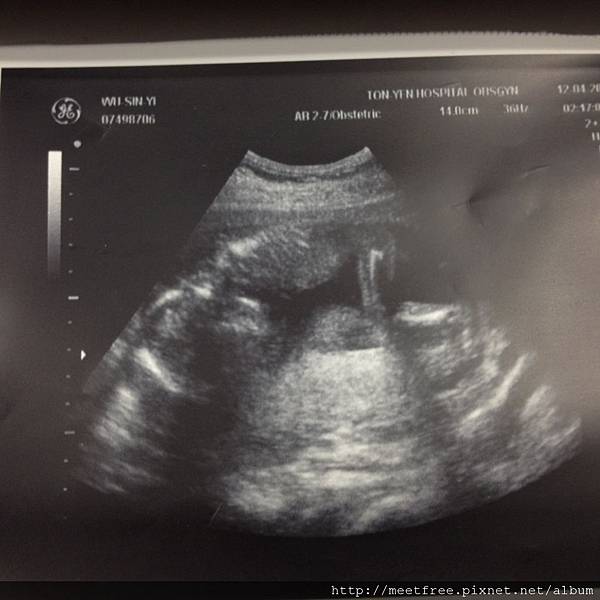

36W2013/04/15 Mon.(一)

等了一個半小時,終於輪到照超音波了,

小妞一開始就正面朝我們,看到眼睛、鼻子、尖(?!)下巴,駱爸比卻說好像是厚嘴唇耶XD,